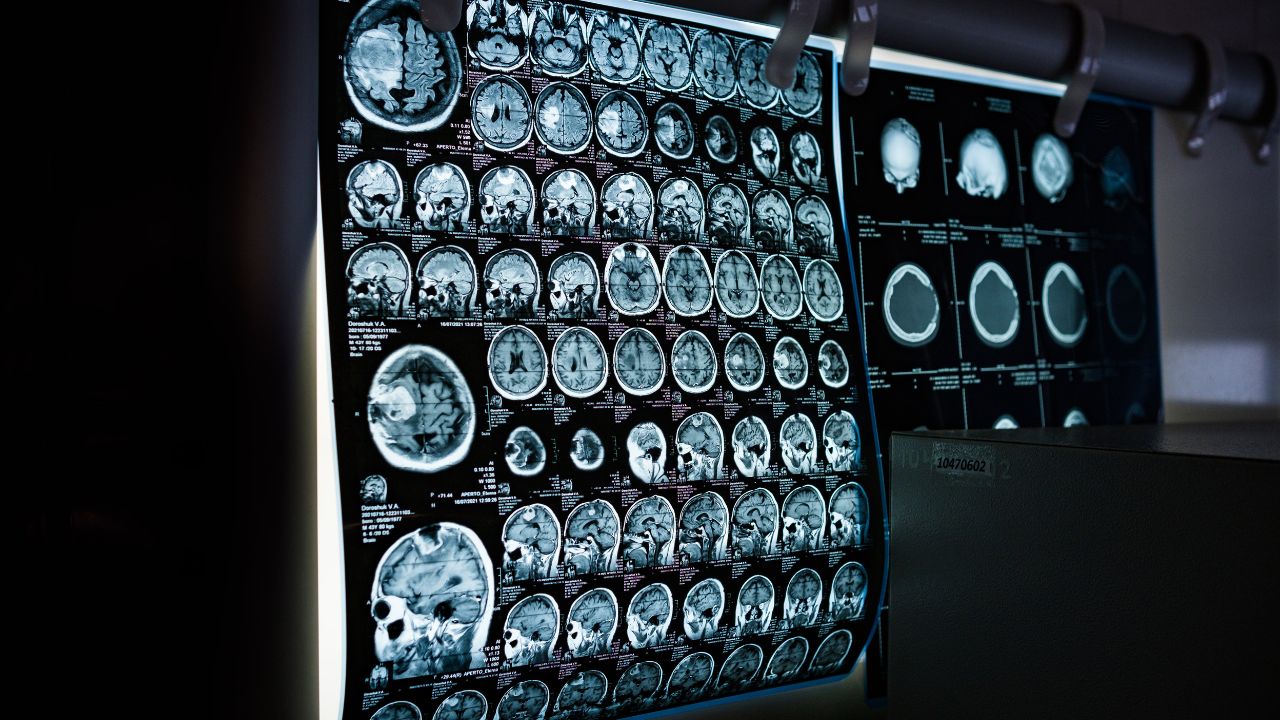

Why Quality Assurance Matters in Digital Radiography

Digital radiography delivers faster results and improved workflow, but consistent quality requires more than advanced detectors. Without structured X-ray QA, imaging centers risk inaccurate results, higher repeat rates, and unnecessary radiation exposure.

Investing in digital radiography equipment is only part of the solution—QA protocols guarantee that technology performs at its peak.